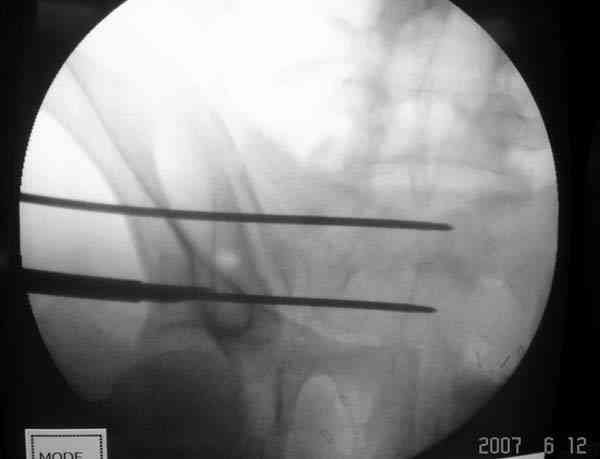

Применение длинных (7 мм каннюлированных, с резбой на всем протяжении

от компании Mercury) шурупов, проведенных между двумя илиосакральными

сочленениями нейтрализирует деформацию до наступления сращения.

На другом конце затягивание гайкой создает эффект болта-стяжки.

Сверло-направитель в 3.2 мм проводится вручную без применения дрели, и

длина в 46 см обычно достаточна до захвата следующего

илио-сактрального сочленения.

Проведение сверла под неврологическим мониторингом уменьшает риск

повреждения нервов во время операции.

Имя     : Mercury sacroiliac screw 2.jpg

Тип     : image/jpeg

Размер  : 30564 байтов

Описание: отсутствует

Url     : http://weborto.net:8080/pipermail/ortho/attachments/20070619/660e38d0/attachment-0006.jpg